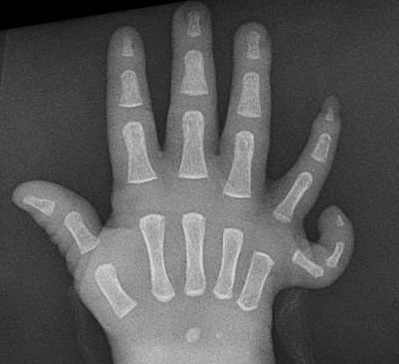

Ulnar-Mammary Syndrome can be expressed differently in family members – even if they have the same variant in their gene. The symptoms may include limb anomalies ranging from malformation or duplication of fingernails to a congenital absence of one of the bones of the arm (ulna), and/or underdevelopment of mammary and sweat glands.